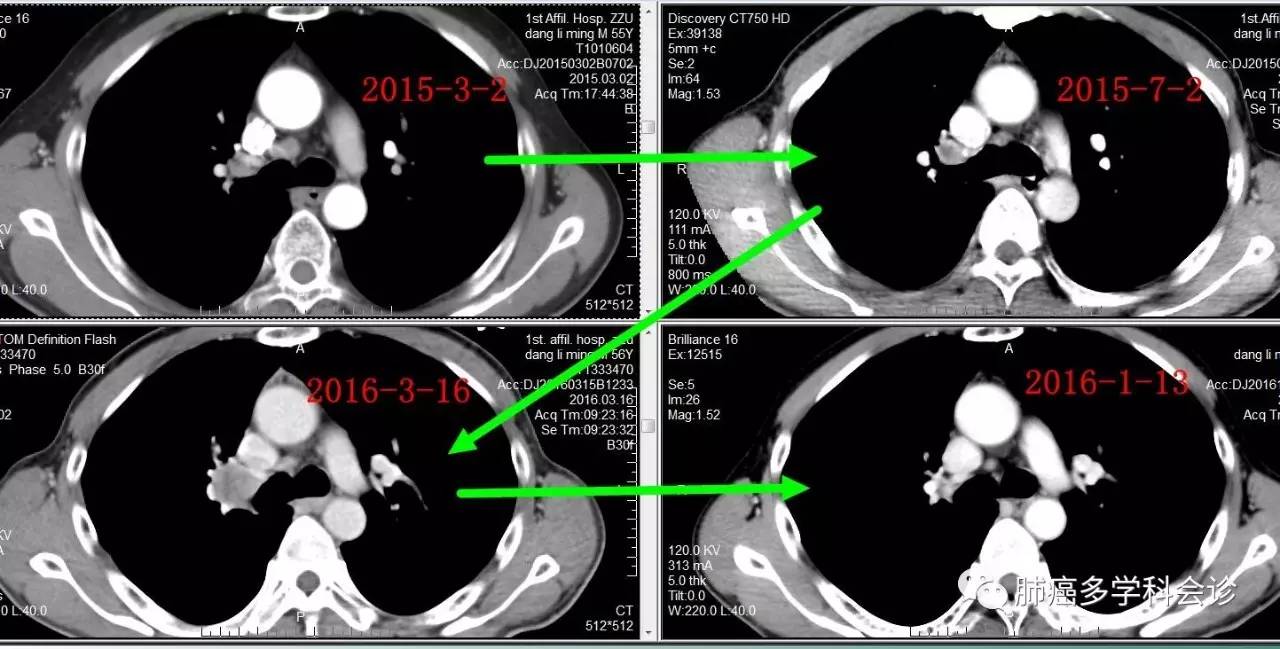

2016 年 3 月复查发现胸部肿瘤较前增大明显,确认为疾病进展,尝试奥希替尼,肿瘤再度缩小。

2016 年 10 月复查 CT 发现疾病又进展,给予“培美曲塞+卡铂”化疗 2 周期。患者因经济困难未能继续治疗。

微信图片_20170705104705.jpg微信图片_20170705104708.jpg下图显示了从诊断到吉非替尼治疗,进展后再用奥希替尼,肺原发灶和转移淋巴结大小的变化过程: